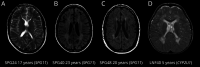

Results: We evaluated 126 patients (101 children and 25 adults) with ages ranging from 1 month to 74 years. We obtained a first molecular diagnosis by singleton WES in 59% of cases, which increased to 68% after annual reanalysis, and reached 72% after WGS was performed in 16 of the remaining negative cases. We identified variants in 57 different genes among 91 diagnosed cases, with the most frequent being RNASEH2B, EIF2B5, POLR3A, and PLP1, and a dual diagnosis underlying complex phenotypes in 6 families, underscoring the importance of genomic analysis to solve these cases. We discovered 9 candidate genes causing novel diseases and propose additional putative novel candidate genes for yet-to-be discovered GWMD.

Figures